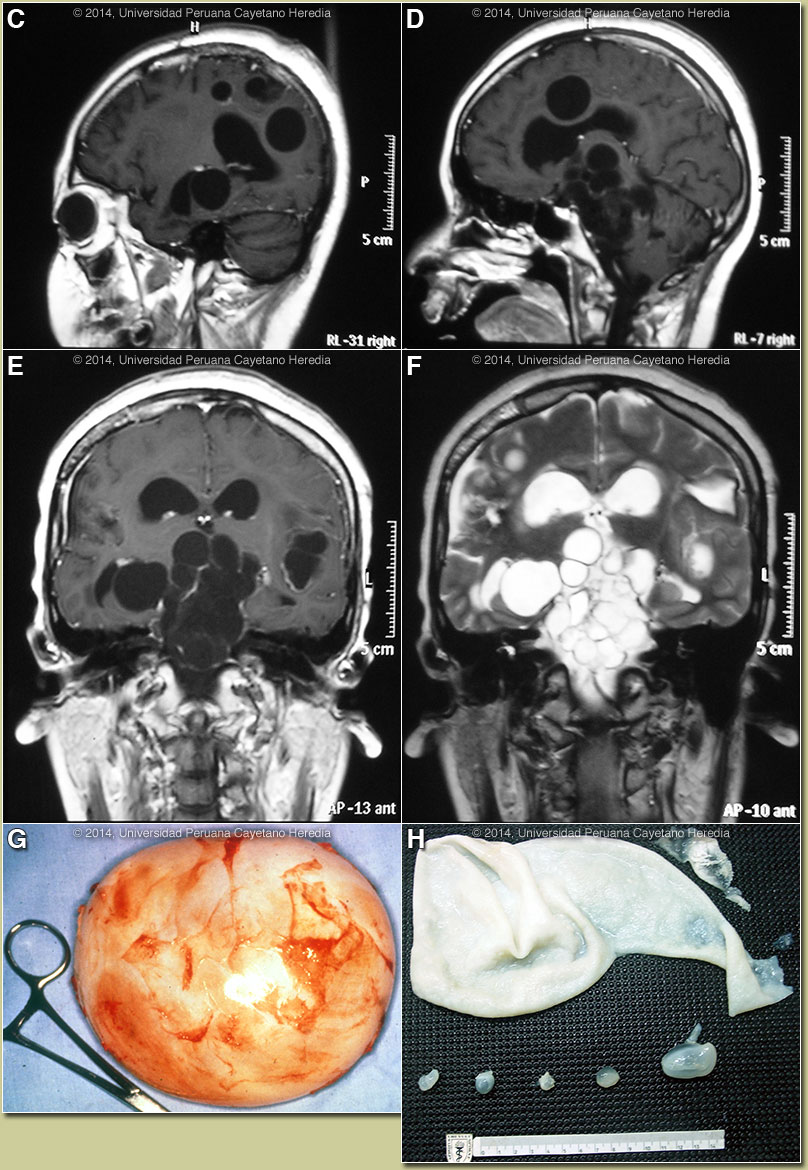

The differential diagnosis, based on radiologic findings, for a cerebral hydatid cyst includes cystic glial tumors, cerebral abscesses, arachnoid cysts, paraventricular ependymal cysts, neurocysticercosis with giant cysts, coenurosis, cystic primary tumor, cysts of the lateral ventricles, traumatic or postsurgical porencephalic cysts, and porencephalic cysts that develop after surgery performed to remove a hydatid cyst. Human hydatid disease secondary to Echinococcus granulosus is caused by the larval form of this dog tapeworm. Humans ingest the tapeworm eggs in environments contaminated by canine feces and become accidental intermediate hosts. This patient had ongoing exposure to dogs while her parents were working raising cattle and sheep. Sheep are the normal intermediate hosts. In general, disease is diagnosed in adulthood as larval cysts expand slowly over years or decades, becoming symptomatic as they impinge on other structures by virtue of their size. The cysts contain hundreds of viable protoscoleces capable of becoming adult tapeworms upon ingestion by a definitive host such as the dog. The internal germinal membrane lining the cyst produces new protoscoleces on an ongoing basis. Each protoscolex is capable of becoming a new daughter cyst should the original cyst rupture or be ruptured. Cystic hydatid disease due to E. granulosus is common in sheep and cattle raising areas worldwide. Most primary infections involve a single cyst. In adults, 65% of solitary cysts are found in liver, 25% in lung and the rest in a wide variety of other organs including kidney, spleen, heart, bone and brain. Surgery is the standard and most effective treatment for intracranial hydatid cysts. The goals of surgery are the removal of the entire intact cyst without rupture and the prevention of parasitic spread and additional neurologic deficits. A large bone flap should be performed; it should be wide enough to allow safe delivery of the cyst away from the skull edges. The removal of hydatid cysts can be achieved by using Dowling’s technique, which involves forcing saline around and under the intact cyst to separate it from the brain parenchyma and removing the cyst intact. Injection of hypertonic saline into the cyst to kill the protoscoleces followed by aspiration and dissection of the membrane is less desirable. Overall, however, catastrophic cyst rupture occurs during up to 25% of operations. Our patient underwent 3 operations on the 3 large parenchymal cysts prior to transfer to us and tragically a cyst rupture did occur on one occasion. MRI on arrival at our hospital is shown in Images C-F and demonstrates the extensive and incurable brainstem involvement now present. Intact and opened cysts from other patients are shown in Images G & H. Albendazole should be immediately instituted in ruptures whether they be spontaneous, post-traumatic or the result of a surgical accident. Praziquantel is the most potent scolicidal drug and is the drug of choice for all adult tapeworms. In hydatid disease, praziquantel is unlike albendazole and does not penetrate the cyst wall or produce measurable concentrations in cyst fluid. Praziquantel is also ineffective against the germinal membrane of cysts, but is able to reliably and quickly kill free protoscoleces [Acta Trop. 2009 Aug;111(2):95-101]. Thus, praziquantel is useful as an acute therapy when a cyst ruptures (spontaneously, or intra-operatively due to surgical mishap) and scoleces are lying free before encysting again. Combined praziquantel and albendazole for medical therapy of liver or lung hydatid has been reported in several small, uncontrolled series and experimental protocols examining combination therapy using are underway in several places. Our patient received 5 months of albendazole and praziquantel after her surgeries but was receiving palliative care only prior to her admission to us. Although the prognosis is desperate, at present the patient is awaiting surgical extirpation of the cysts pressing on the brainstem and at least aspiration and instillation of hypertonic saline to the parenchymal cysts. We have instituted indefinite therapy with albendazole 800 mg/day plus praziquantel 25 mg/kg/day. |